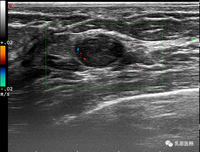

新华社圣彼得堡3月7日电(记者陈畅)俄罗斯研究机构近日训练出一种能够快速识别计算机断层扫描(CT)影像的人工智能,可以协助医生诊断早期乳腺癌。

据塔斯社报道,俄罗斯圣彼得堡国立电子技术大学与阿尔马佐夫国家医学研究中心共同开发了一款医疗诊断辅助软件系统,其核心是神经网络这种人工智能技术。经过训练的神经网络能够自动处理上传至服务器的患者CT影像,标记出具有肿瘤特征的区域。标记后的影像会被发送给医生,由医生作出最终诊断。

研究人员表示,过去解读一张CT影像通常需要一天,而这项技术的影像分析过程仅需几分钟,还可将临床误诊的概率降低约20%。